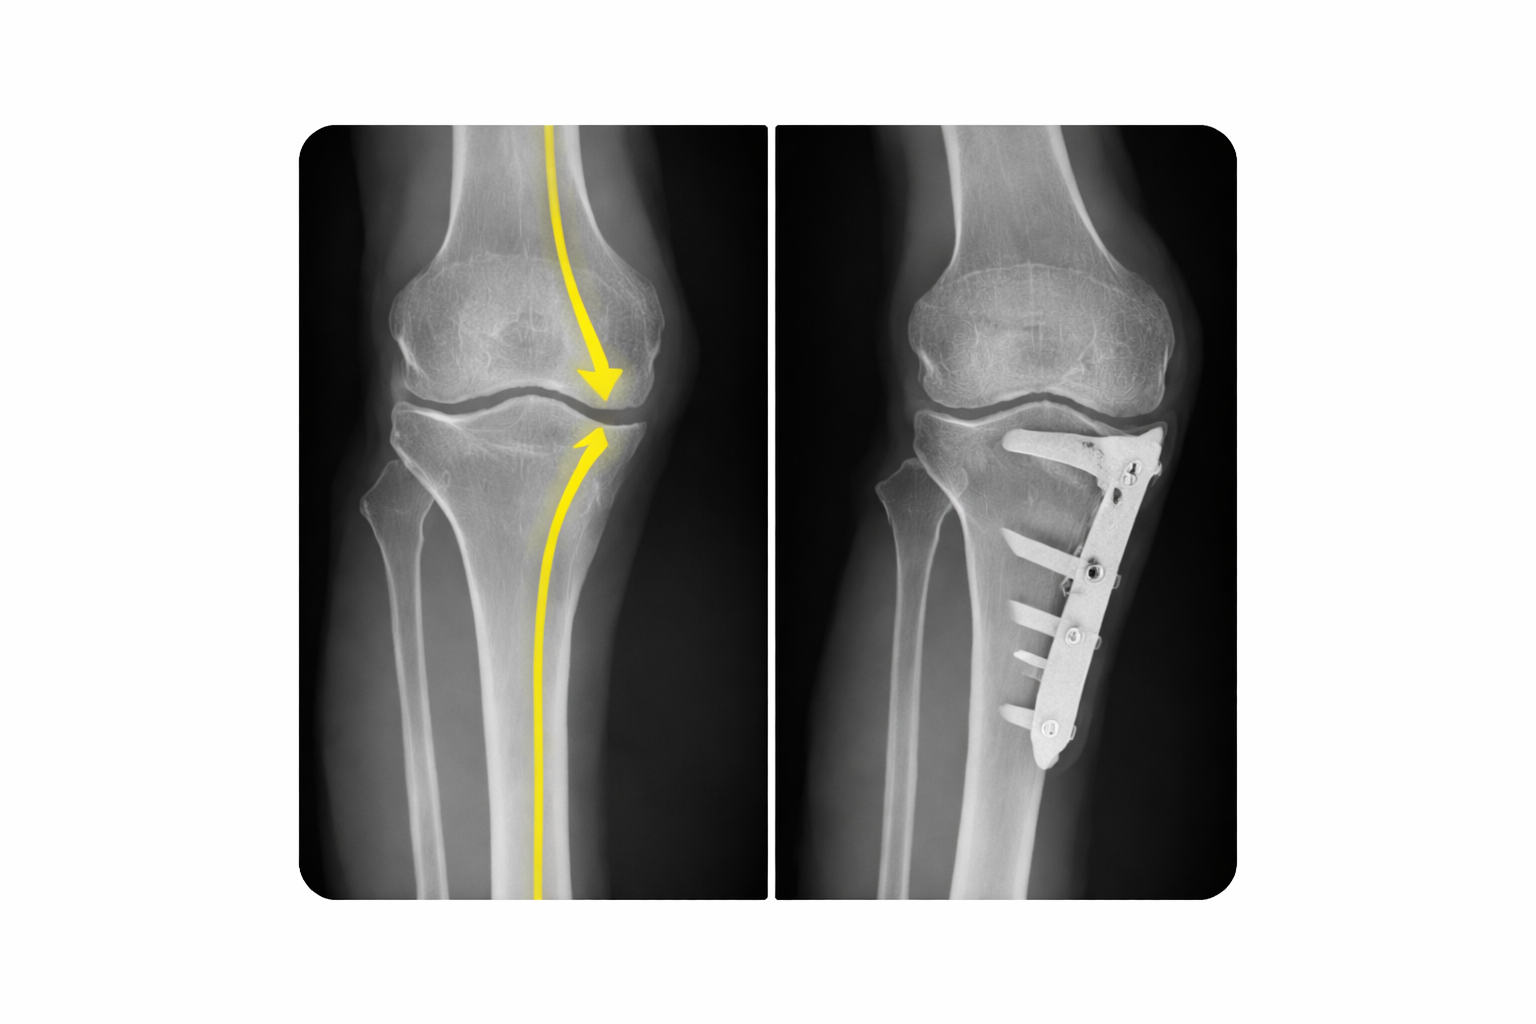

Joint Deformity Correction is a specialized field focused on restoring the natural alignment of bones. When legs are bowed (varus) or knock-kneed (valgus), weight is distributed unevenly, leading to rapid cartilage wear in one part of the knee.

At Trinay Orthopedic Hospital, we use Osteotomy (precise bone cutting and realignment) to shift the weight-bearing axis back to the healthy center of the joint, avoiding the need for a premature replacement. Our goal is joint preservation and longevity.

• Bow Legs (Genu Varum): Overloading the inner knee. Treated with High Tibial Osteotomy (HTO).

Our gold standard is to keep your natural joint as long as possible. High Tibial Osteotomy acts as a "biological knee replacement," letting you return to high-impact activities like running or heavy labor that artificial joints might not support.